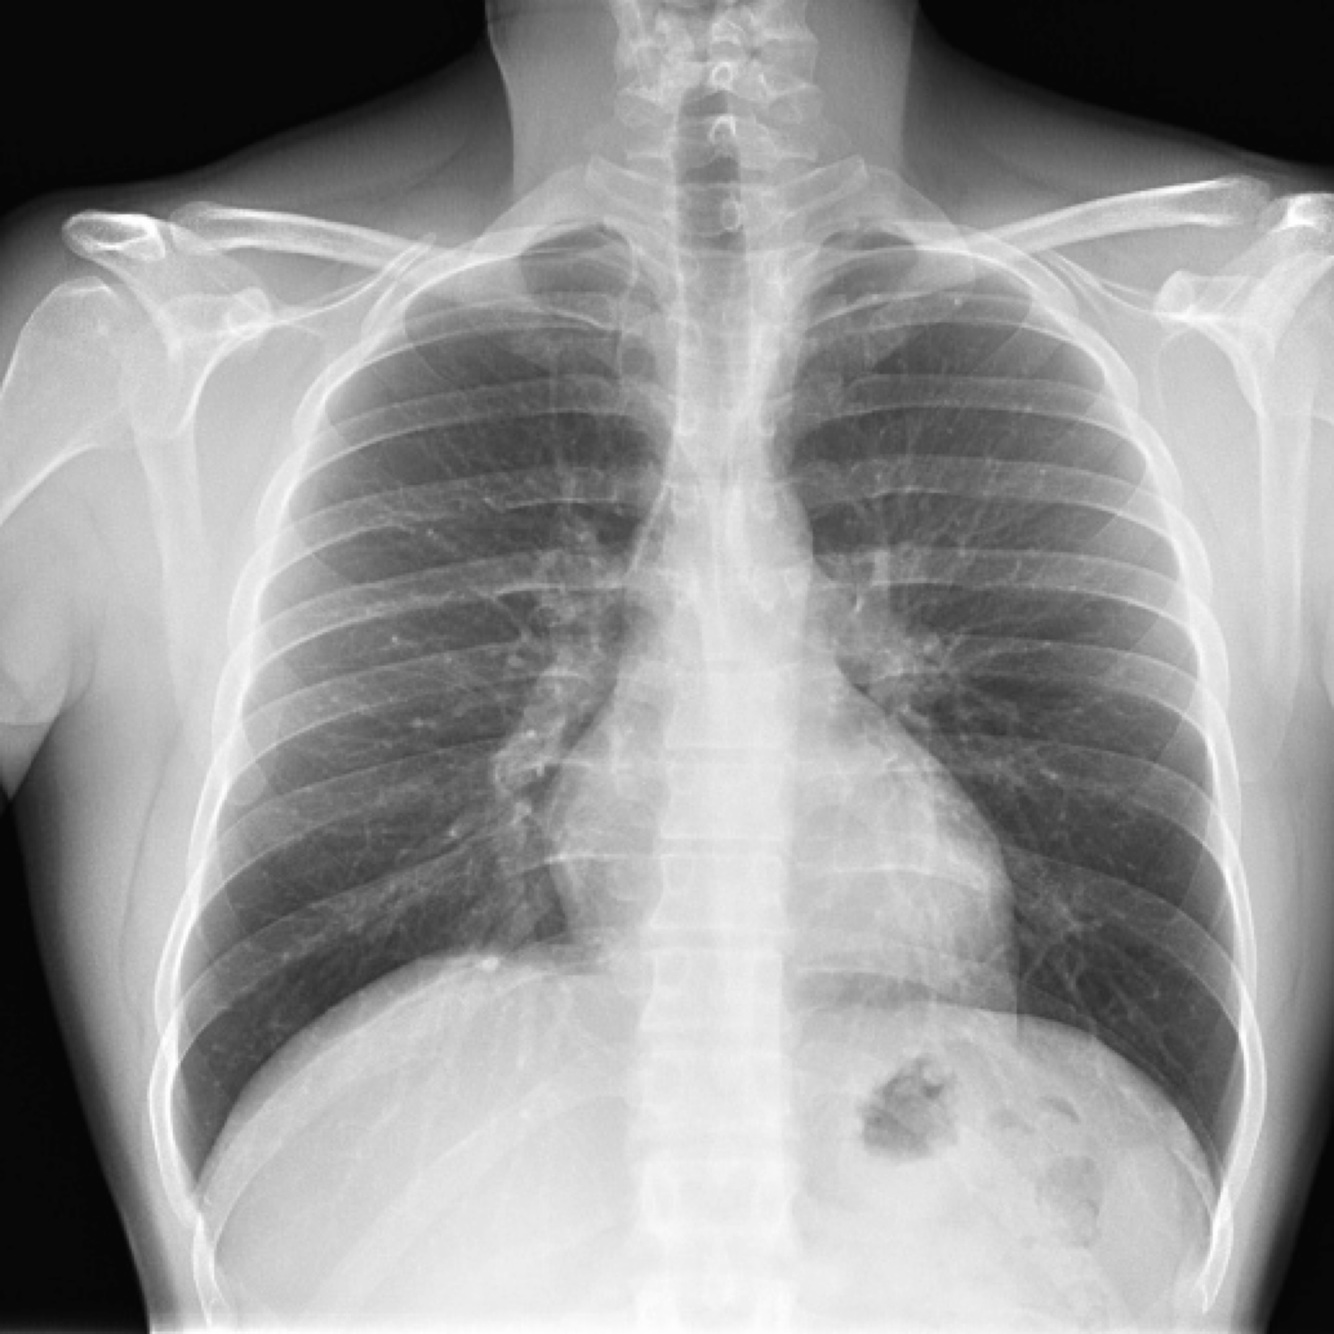

22

Q

¿Qué proyección es la siguiente?

A

PA